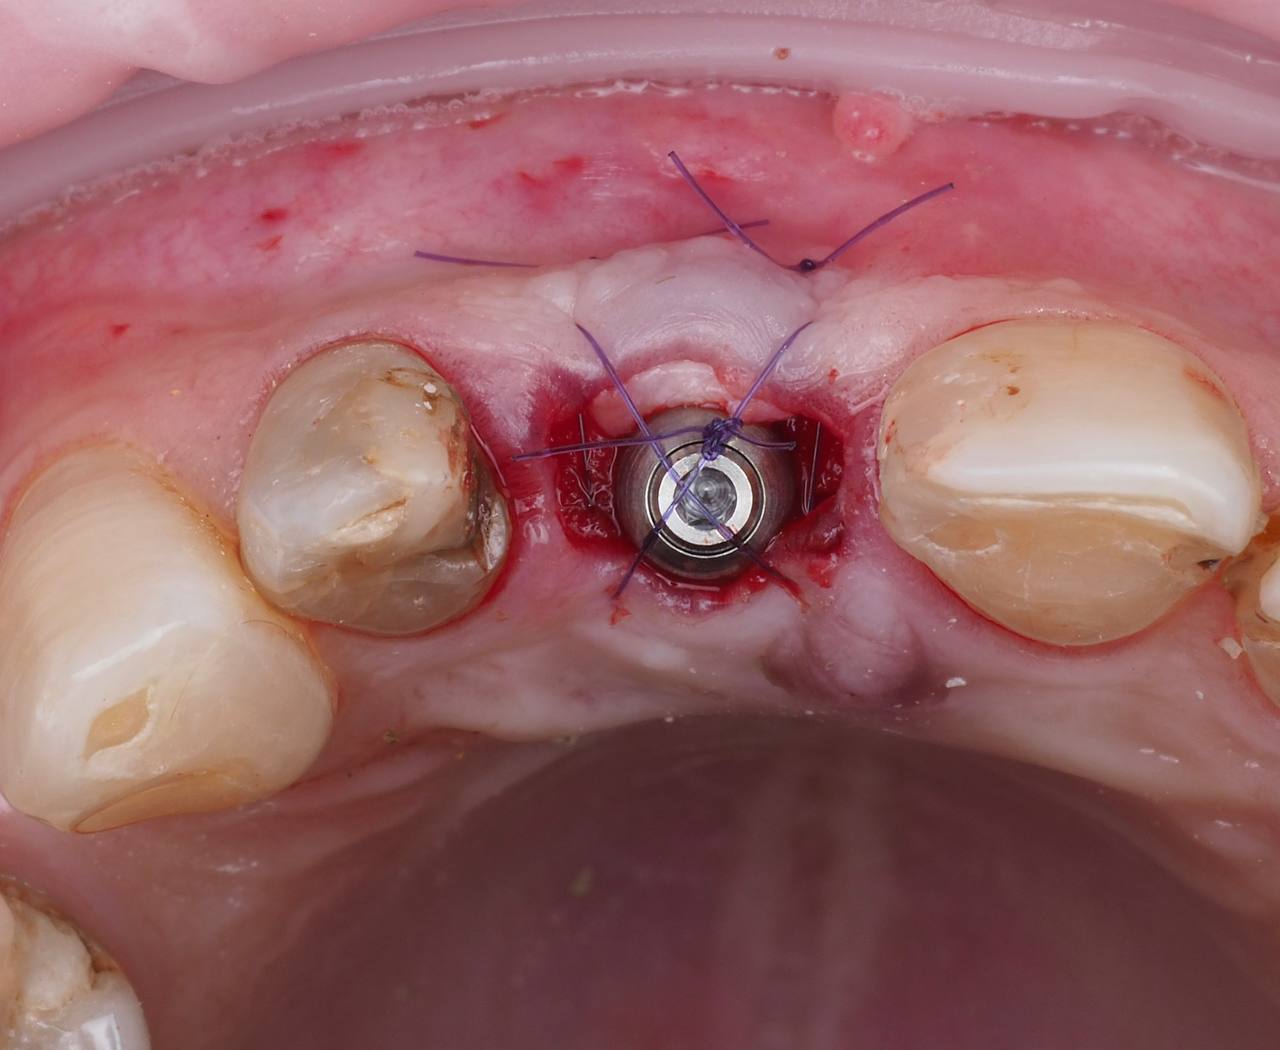

Одномоментная имплантация 1.1

AnyRidge, мультиюнит Octa, CCT, временная коронка